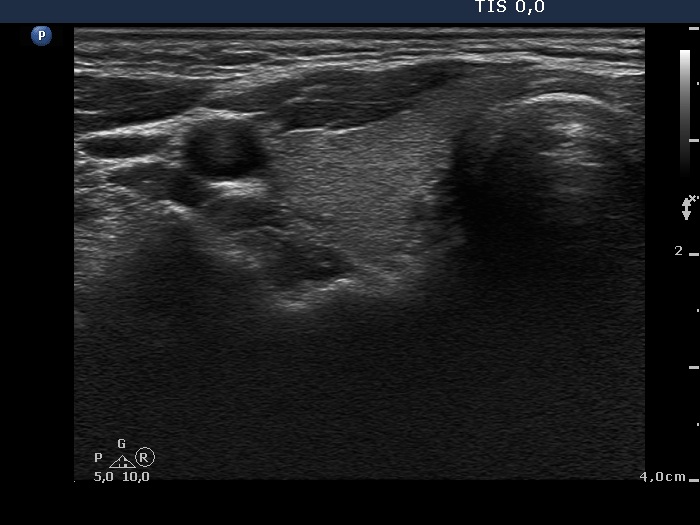

Second examination 9 months later (2nd row of images)

Clinical data: The patient had no complaints except for a 6 kg weight in gain.

Palpation: unchanged.

Results of blood tests: euthyroidism on daily 10 mg methimazole (TSH 3.58 mIU/L, FT4 12.7 pM/L).

Ultrasonography: Compared with the first examination, the thyroid has decreased in size and the echo structure became less hypoechogenic. The vascularization remained unchanged.

Suggestion: daily 5 mg methimazole.